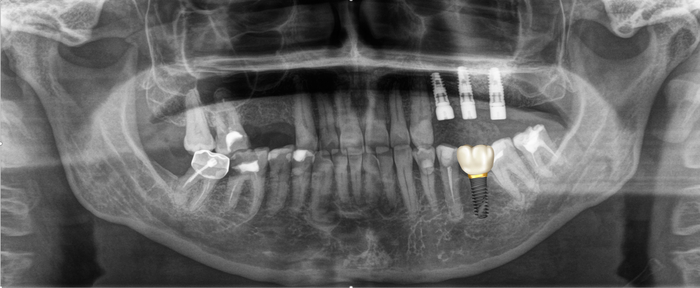

Ниже панорамный снимок, где хорошо видно, как из-за длительного (овер 10 лет) отсутствия 6-го зуба на нижней челюсти слева (на снимке справа) соседние зубы – седьмой и восьмой – наклонились в сторону отсутствующего.

(На верхней челюсти с этой же стороны были удалены четвертый, шестой и седьмой зубы. На их месте установлены имплантаты и проведен синус-лифтинг. Пятого зуба у пациентки не было.

Если посмотреть внимательно, то можно обратить внимание на то, что седьмой и восьмой зубы стоят в зубном ряду выше, чем с противоположной стороны:

Вот результат после установки временной коронки и удаления минивинта:

Временные коронки делаются из фрезерованной пластмассы, поэтому не рентгеноконтрастны, хотя, если посмотреть внимательно, то можно увидеть неявные очертания коронок.